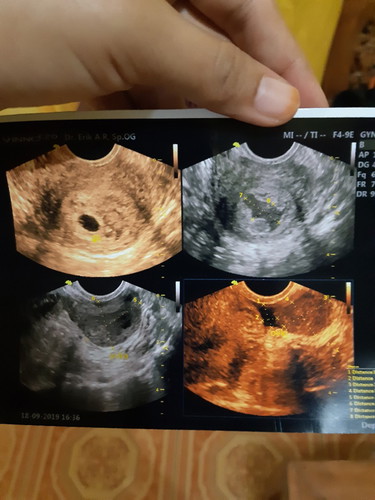

alhamdulillah tadi usg udah keliatan kantongnya tapi sedihnya ternyata aku ada kista dan ada bekuan darah soalnya sempat jatoh 3 hari yg lalu(mungkin penyebabya jatoh ini kata dokter). Disuruh bedrest total, 2 minggu lagi disuruh balik lagi buat liat bekuan darahnya dah ilang/belum dan kista nya mngecil atau gak.. doain ya bunda² kehamilan aku lancar, sehat gak ada kurang satu apapun begitu juga dengan bunda² yg lagi hamil jg..?